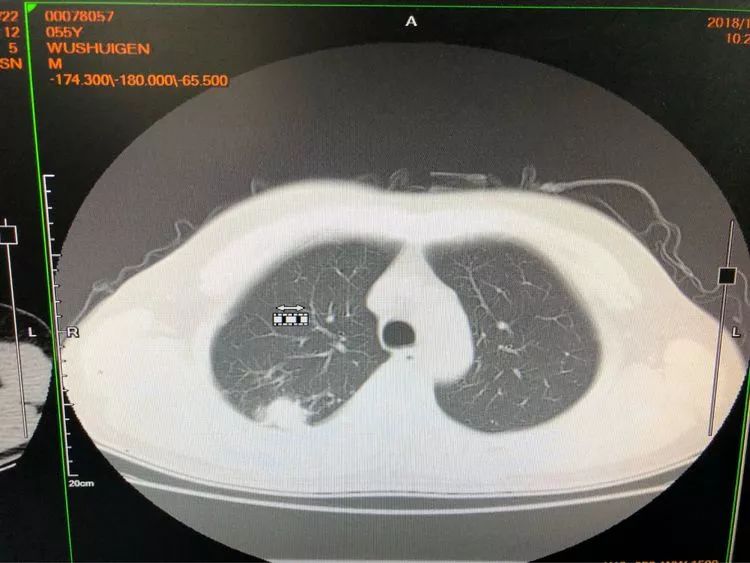

第三例 吴大伯今年55岁,右上肺后段结节样病变,伴有钙化,一般这种情况大家都会觉得是结核球。

由于患者门诊抗结核治疗病灶稍增大,医生们经商议最终决定穿刺。虽然从影像看起来没有穿刺路径,不过没关系,省胸科医院经验丰富的内科医生们可以通过体位来调整。